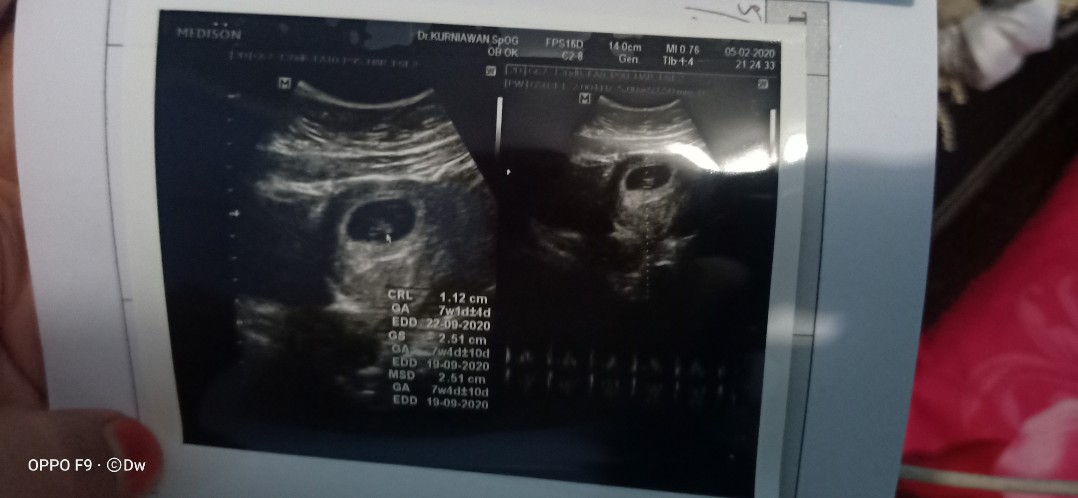

Wajar ga sih di usia 10 minggu masih berbentuk kantong

Itu tulisannya masih 7w bun

Itu d usg 7w bun bukan 10w

Itu 7 minggu bun.. Wajar

Itu masi 7 week :")